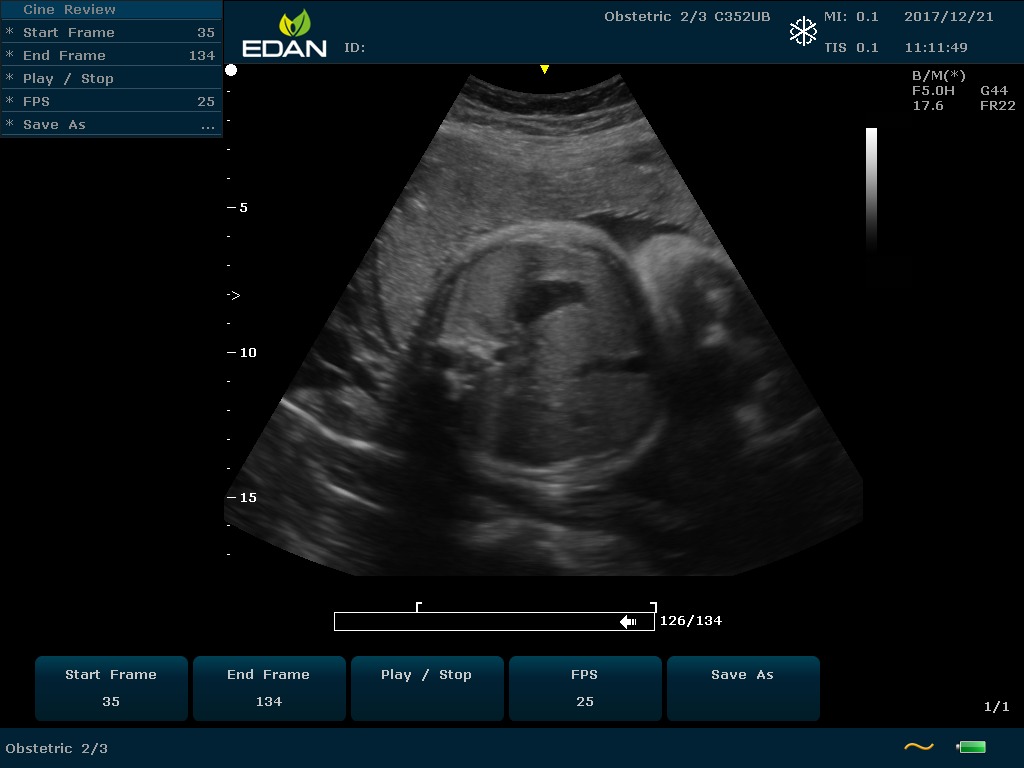

Портативный УЗИ-аппарат среднего класса U60 Edan c цветным допплером — универсальное устройство, удивляющее сочетанием компактности и многофункциональности.

Особенность U60 Edan — расширенное применение. Ультразвуковой аппарат рекомендован для абдоминальных исследований, гинекологии и акушерства, кардиологии, педиатрии, урологии, изучения малых органов, сосудов. Для U60 Edan используются конвексные, линейные, фазированные и внутриполостные датчики.

Передовые технологии позволяют повысить качество визуализации в несколько раз. УЗИ-аппарат U60 Edan отличается возможностью быстрой настройки визуализации. Специальные функции позволяют моментально отображать данные за счет быстрой оптимизации параметров. Режимы визуализации: B-mode, M-mode, Color Doppler, Power Doppler Imaging, Pulsed Wave Doppler, Continuous Doppler.